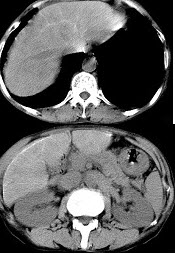

男,40岁有血吸虫感染史,腹胀不适,食欲减退,CT扫描所见如图,最可能的诊断是( )

A:肝炎后肝硬化

B:血吸虫后肝硬化

C:酒精性肝硬化

D:胆汁性肝硬化

E:脂肪肝